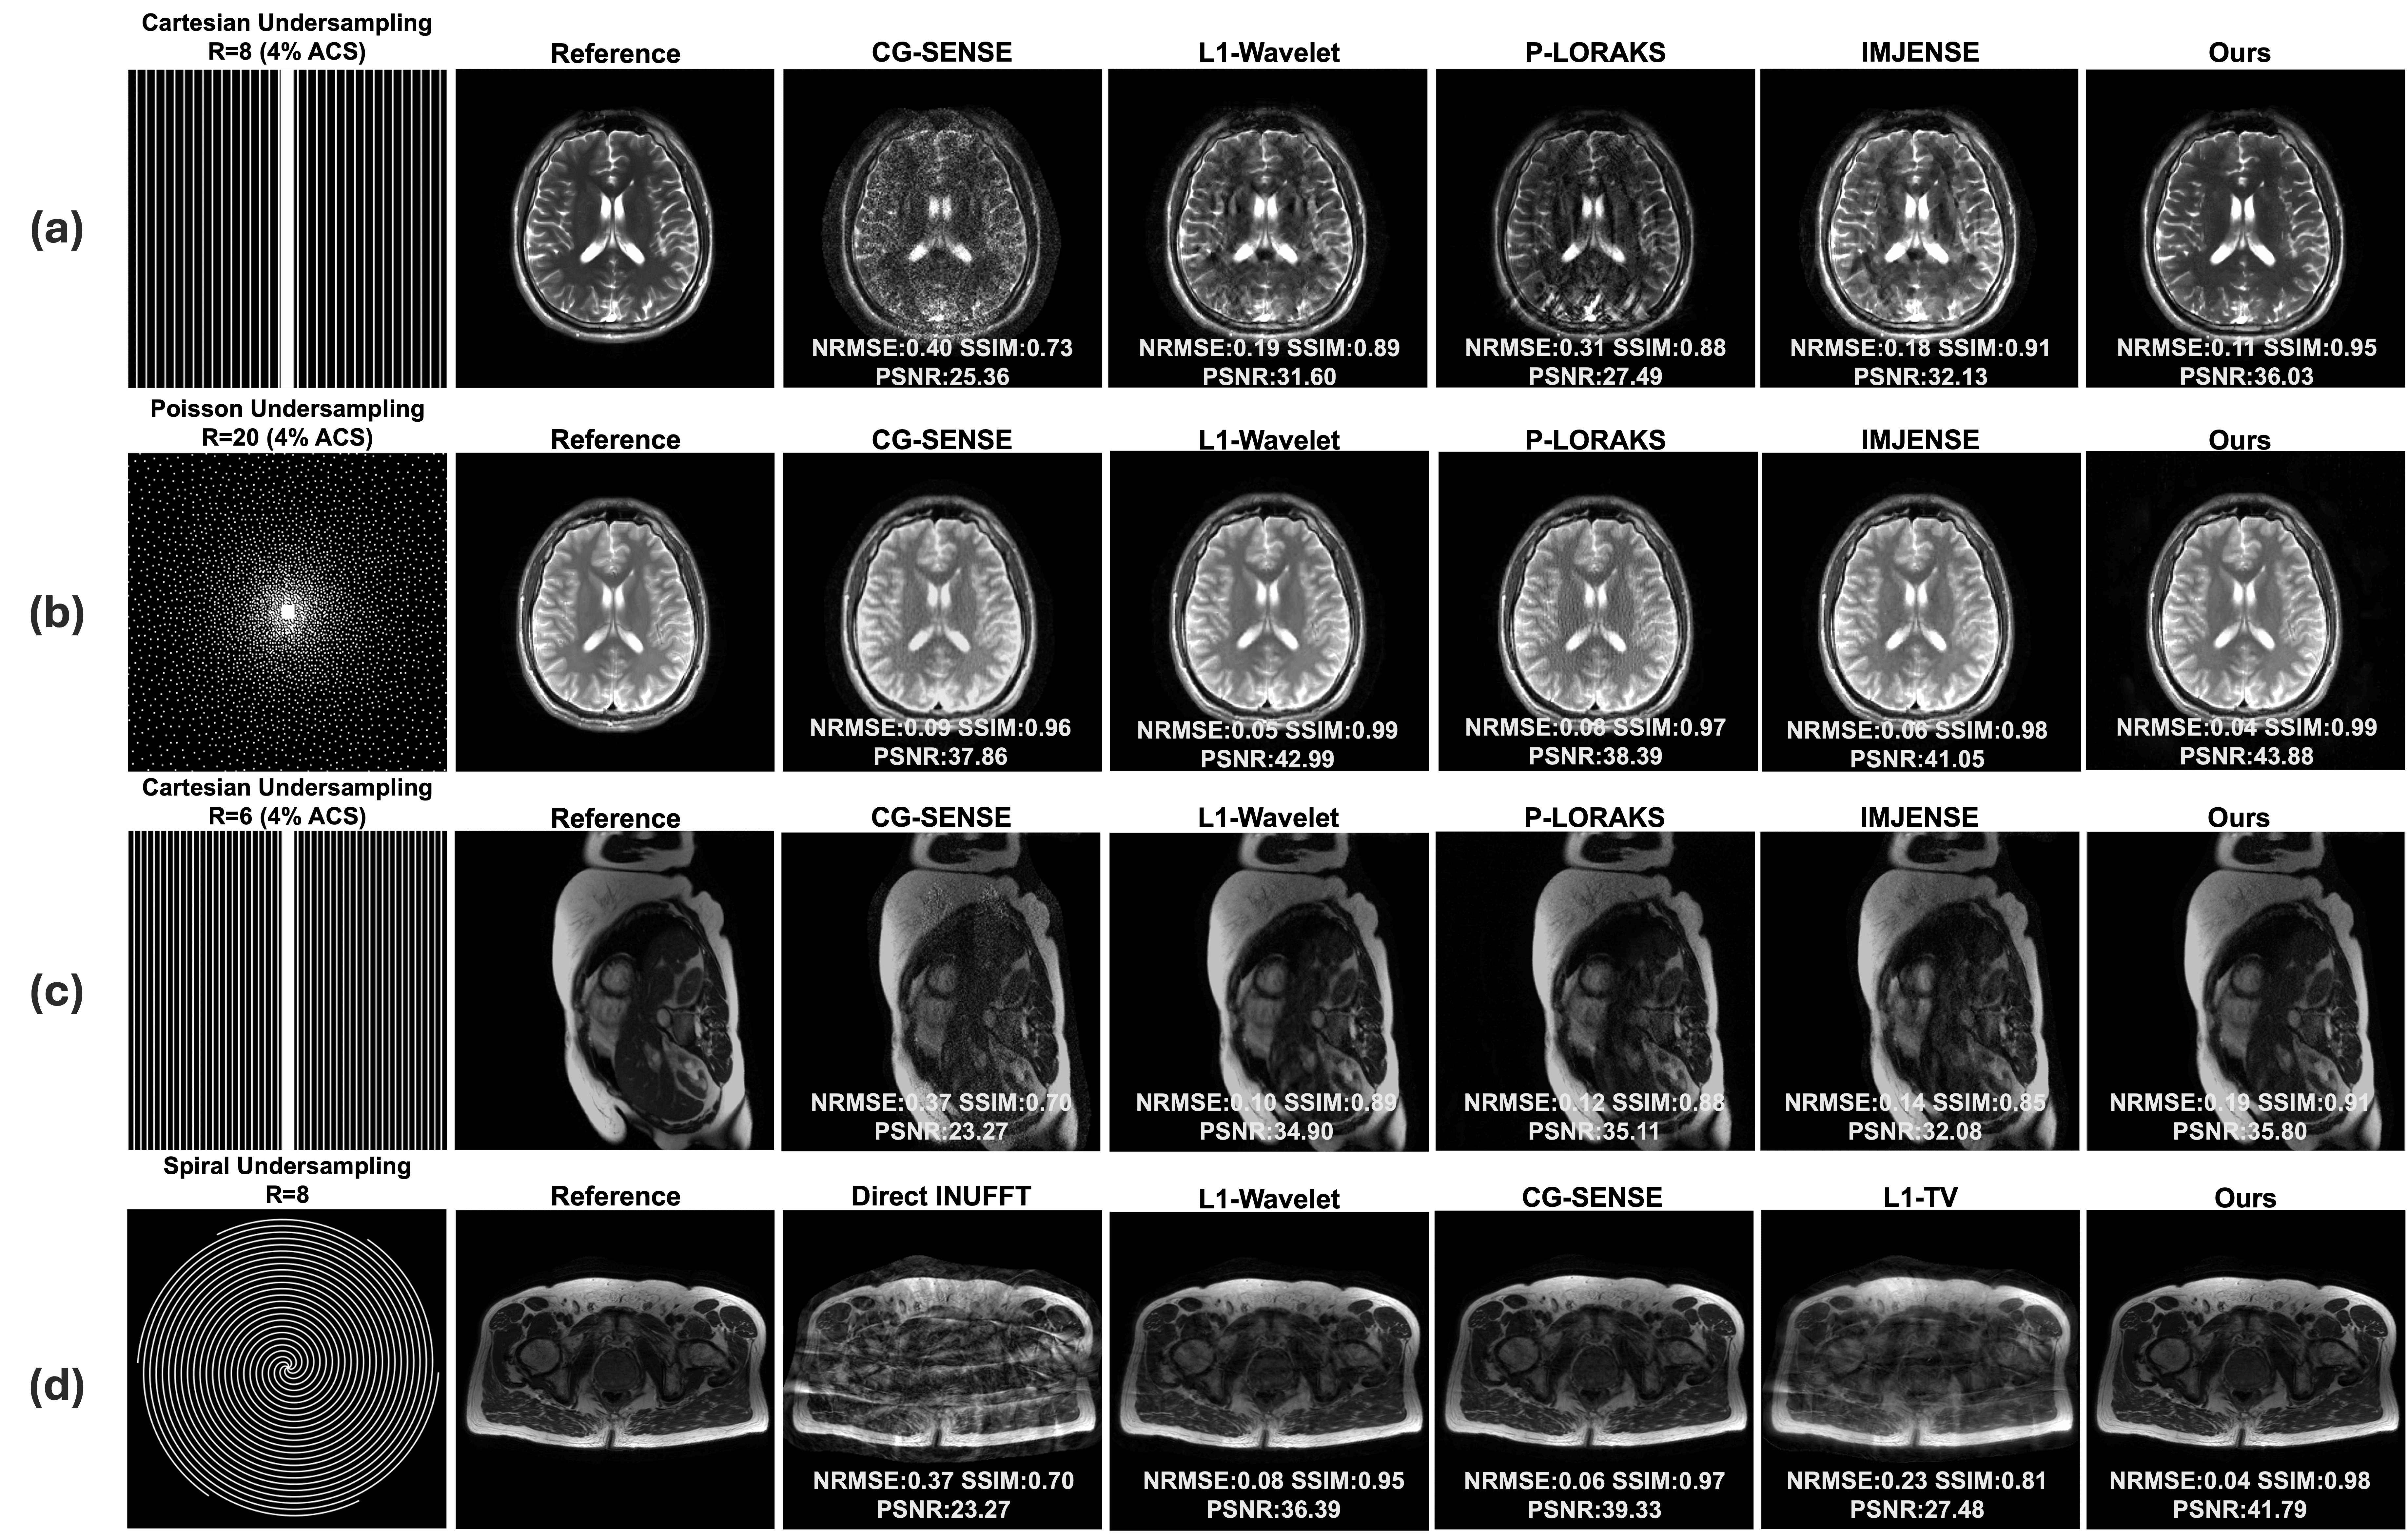

Refer to caption

Figure 4: Ablation study. (a) Decoder comparison with fixed Hash Encoder (i.e., Linear layer vs 1/2/3/6/8 layer MLP). (b) Encoder comparison with fixed Decoder MLP. (c) Loss function weighting comparison. (d) Activation function comparison.

Fig. 4 presents ablation experiments on key components of the bilevel-optimized INR. Fig. 4(a) compares decoders of varying depths against a linear layer under identical hyperparameters. Except for the single-layer MLP, all decoders converge to similar performance based on quantitative metrics. Even a linear layer can decode the positionally encoded features effectively, indicating the encoder’s dominant role in the reconstruction pipeline.

Fig. 4(b) evaluates different positional encoders on a 6×6\times Cartesian undersampled T2-weighted TSE dataset. Without encoding or with frequency encoding, the model struggles to capture fine details in the brain, while dense grid and hash grid encodings yield comparable metrics. However, dense grid requires 20×20\times memory and 15×15\times of training time

Fig. 4(c) focuses on loss-function weighting, tested on a spiral undersampled prostate dataset. The proposed self-weighting scheme in (9) has the best reconstruction quality, capturing correct contrast and detailed structure. No loss weighting causes visible blurriness across the pelvic region. Using Pipe’s density compensation function [43] ranks second, with 0.060.06 NRMSE, 0.970.97 SSIM, and 39.4739.47 dB PSNR compared to 0.040.04, 0.980.98, and 41.7941.79 dB from our approach. Substituting the acquired data for the predicted k-space in each iteration leads to a bad local minimum during training, which shows incorrect contrast and degraded metrics.

We also considered additional hyperparameters such as the MLP’s width and depth, but observed that their influence remains relatively stable across different datasets. Fig. 4 shows that even a linear-layer decoder can produce high-quality reconstructions, demonstrating the positional encoder’s dominant contribution for the reconstruction. For the Hash encoder, we tested a table size of 216\geq 2^{16} and a finest resolution determined by scaling factor b1.5b\geq 1.5, both of which yielded comparable performance across various scans. Overall, over-parameterization with optimized self-regularization provided by weight decay is another reason why the hash-encoded INR-based approach can reconstruct highly accelerated MRI scans.

6.2 Analysis of components of Bilevel Optimized INR

This study also provides experiments to analyze the effect and selection of key components in an INR for scan-specific MRI reconstruction. The main components of an INR are the positional encoder, the decoder MLP, and the loss function. Fig. 4(b) compares no encoding, frequency encoding [24], dense grid encoding [42], and hash grid encoding [33]. Unlike view synthesis, which leverages multiple view images for training, no encoding and frequency encoding are both slow to train and even unable to capture fine MR image details. By contrast, dense grid and hash grid encodings can reconstruct images effectively due to over-parameterization. However, the dense grid demands more memory and training time since it stores weights for every grid corner. Fig. 4(a) compares MLPs of various depths against a linear layer. All decoders achieve similar performance upon convergence, consistent with prior findings [33] that the encoder primarily solves the inverse problem. However, our activation function differs from SIREN [44], which applies sinusoidal activation for view synthesis. In this study, ReLU activation yielded more stable training and was less prone to overfitting, whereas SIREN tended to introduce residual artifacts. We attribute this to: (1) this task is heavily over-parametrized as only a 2D MR image is reconstructed instead of full 3D view like in SIREN, and (2) the implicit regularization from the “dying ReLU” phenomenon [45], which helps limit overfitting. This also explains why previous Hash-encoded INR MRI reconstruction methods [26, 27] often required additional explicit priors, as sinusoidal activation was used. We interpret the loss weighting as a learned density compensation function (DCF). In non-Cartesian reconstructions, DCF emphasizes the higher-frequency components (much smaller in magnitude compared to low-frequency components) to avoid image blurring. A similar rationale applies to INR-based reconstruction: a standard 2\ell_{2} loss in k-space could lead the MLP to learn a conditional mean of the target kk space distribution in the regression task[46]. Our experiments show that a learned self-weighting scheme provides the best performance, displayed in Fig. 4(c).